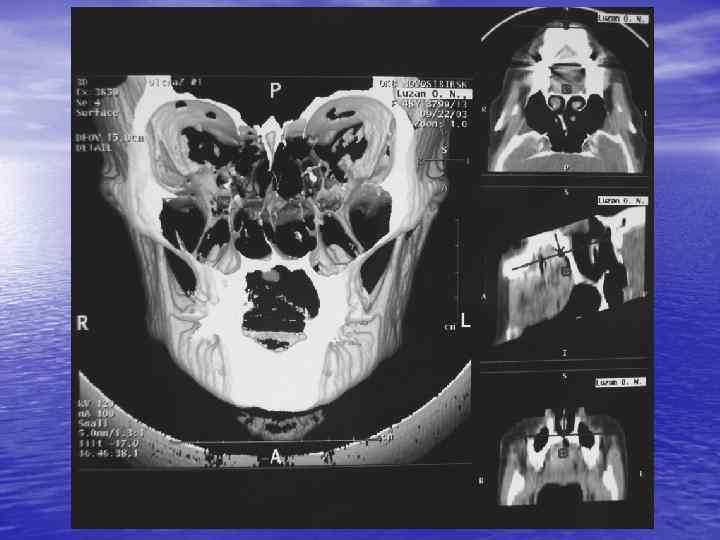

Процесс получения КТ изображения содержит три основных этапа: üизмерение, üреконструкция, üвизуализация. В настоящее время КТ можно использовать для визуализации любой части тела!

Спиральная КТ üНепрерывное вращение рентгеновской трубки вокруг объекта и непрерывное поступательное движение стола с пациентом üЗначительное ускорение процесса сканирования (15 -20 сек) üПринцип объемного сканирования, позволяющий получить непрерывный объем данных при исследовании выбранной анатомической области üШаг стола 0, 5 – 2 мм

Преимущества спиральной КТ: ü Возможность проведения исследования с болюсным ü ü ü ü ü контрастированием Высокая разрешающая способность; Высокая скорость исследования; Получение высококачественных изображений костных структур; Возможность обследования всего тела; Возможность проведения исследования больных под наркозом; Возможность детальной оценки состояния крупных и периферических сосудов в условиях искусственного контрастирования; Высокая информативность метода при черепномозговых травмах в остром периоде; Ранняя диагностика ишемических и геморрагических инсультов; Метод выбора для диагностики заболеваний легких; Планирование лучевой терапии.